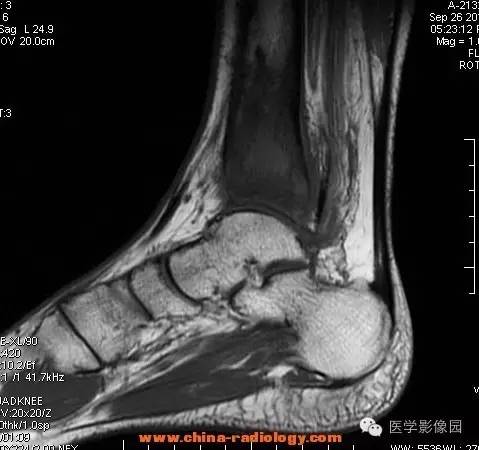

【病例】胫骨骨脓肿1例MR影像表现

影像学表现:胫骨中下段干骺端不未规则形长T1长T2信号,T2WI见不完整环形稍低信号影,T2脂肪抑制低信号更明显,并见胫骨下段及踝关节后外侧软组织呈弥漫稍高信号,增强明显不均匀强化,增强见低信号环内有环形强化影。

影像学表现:表现为长骨干骺端有椭圆形密度减低区,边缘有清晰的骨质硬化,病变与邻近正常骨髓腔境界清楚。MRI上T1WI呈低信号,少数呈等信号,T2WI多为混杂高信号,增强扫描可见环状强化,强化的脓肿壁薄而均匀。